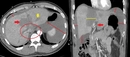

Karaciğer Lekeleri: Belirtileri ve TedavisiKaraciğer, vücudumuzun en büyük organlarından biri olup, birçok önemli işlevi bulunmaktadır. Karaciğer lekeleri, bu organ üzerinde meydana gelen anormal değişiklikler veya lezyonlardır. Bu lekeler, genellikle tesadüfen yapılan görüntüleme testleri sırasında fark edilir ve çeşitli nedenlerden kaynaklanabilir. Bu makalede, karaciğer lekelerinin belirtileri, nedenleri ve tedavi yöntemleri detaylı bir şekilde incelenecektir. Karaciğer Lekeleri Nedir?Karaciğer lekeleri, karaciğer dokusunda meydana gelen anormal hücresel büyümelerdir. Bu lezyonlar, iyi huylu (benign) veya kötü huylu (malign) olabilir. İyi huylu lezyonlar genellikle sağlık açısından tehdit oluşturmazken, kötü huylu lezyonlar kanserin bir belirtisi olabilir. Karaciğer Lekelerinin BelirtileriKaraciğer lekeleri genellikle belirti vermez, ancak bazı durumlarda aşağıdaki belirtiler görülebilir:

Karaciğer Lekelerinin TanısıKaraciğer lekelerinin tanısı genellikle aşağıdaki yöntemlerle yapılır: